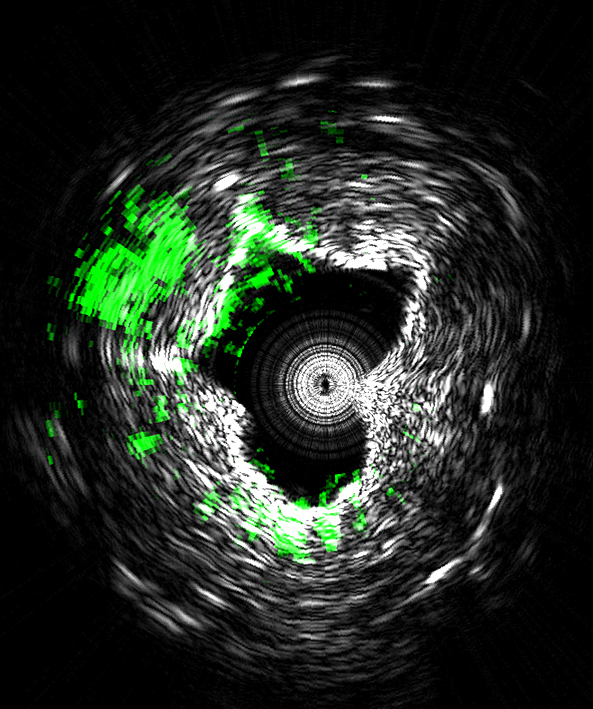

This image is taken using a new type of medical imaging technology that could diagnose cardiovascular disease by measuring ultrasound signals from molecules exposed to a fast-pulsing laser. The system, called intravascular photoacoustic imaging, takes precise three-dimensional images of plaques lining arteries and identifies deposits that are likely to rupture and cause heart attacks. This cross-sectional view of an artery shows lipids (green) deposited inside the arterial wall Black and white indicate contrast showing the cross-sectional geometry.A publication-quality image is available at http://www.purdue.edu/uns/images/2014/cheng-arteries.jpg.

(Photo Credit: (Purdue University Weldon School of Biomedical Engineering image/Ji-Xin Cheng))